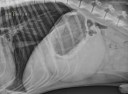

RadioQuiz 24 – Abdomen gonflé et tendu